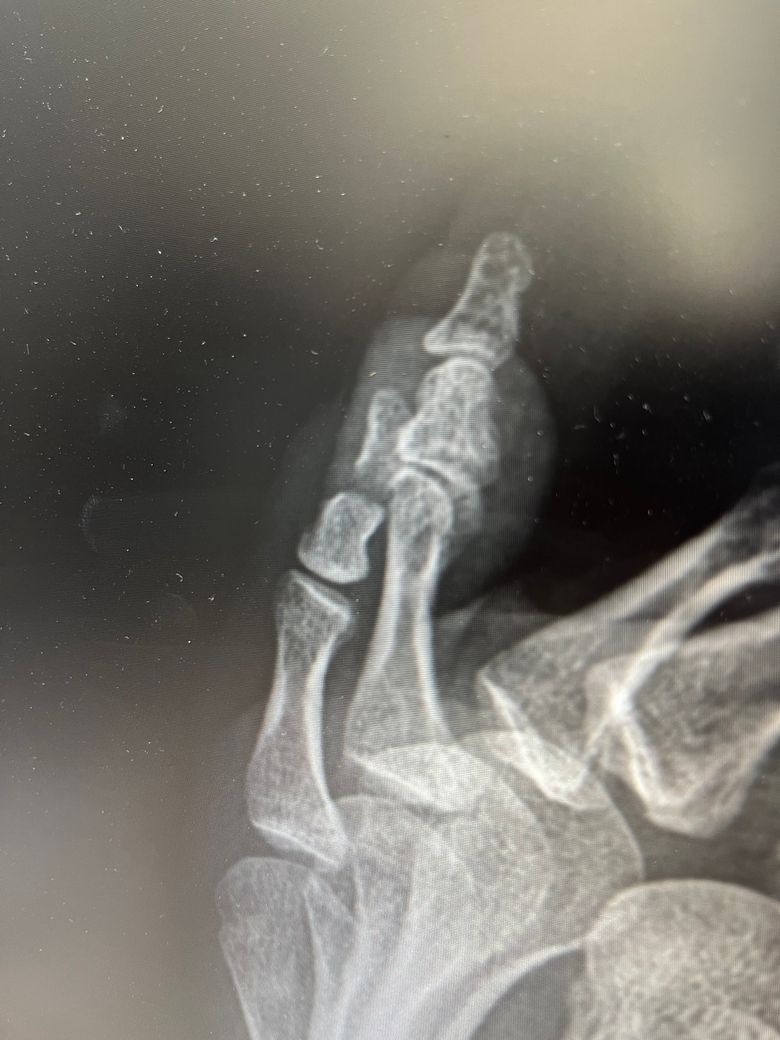

새끼발가락 골절, 수술 필요할까요?

3일전 골절 되었고 옆으로 봤을때 사진입니다

현재 테이핑+ 반깁스 중입니다

수술 추천하시는데 고민이 되어서요

비수술치료는 어려울까요?

• 1번 째 사진

새끼발가락 골절의 경우 비수술적 치료가 가능한 경우가 많습니다. 테이핑과 반깁스는 일반적으로 초기 치료에 효과적일 수 있어 골절이 단순하고 이동이 적은 경우 수술 없이도 회복이 가능합니다. 그러나 골절의 위치와 변위 정도에 따라 수술이 필요할 수 있으므로 정확한 진단을 바탕으로 의사와 상의해 결정하는 것이 중요합니다!